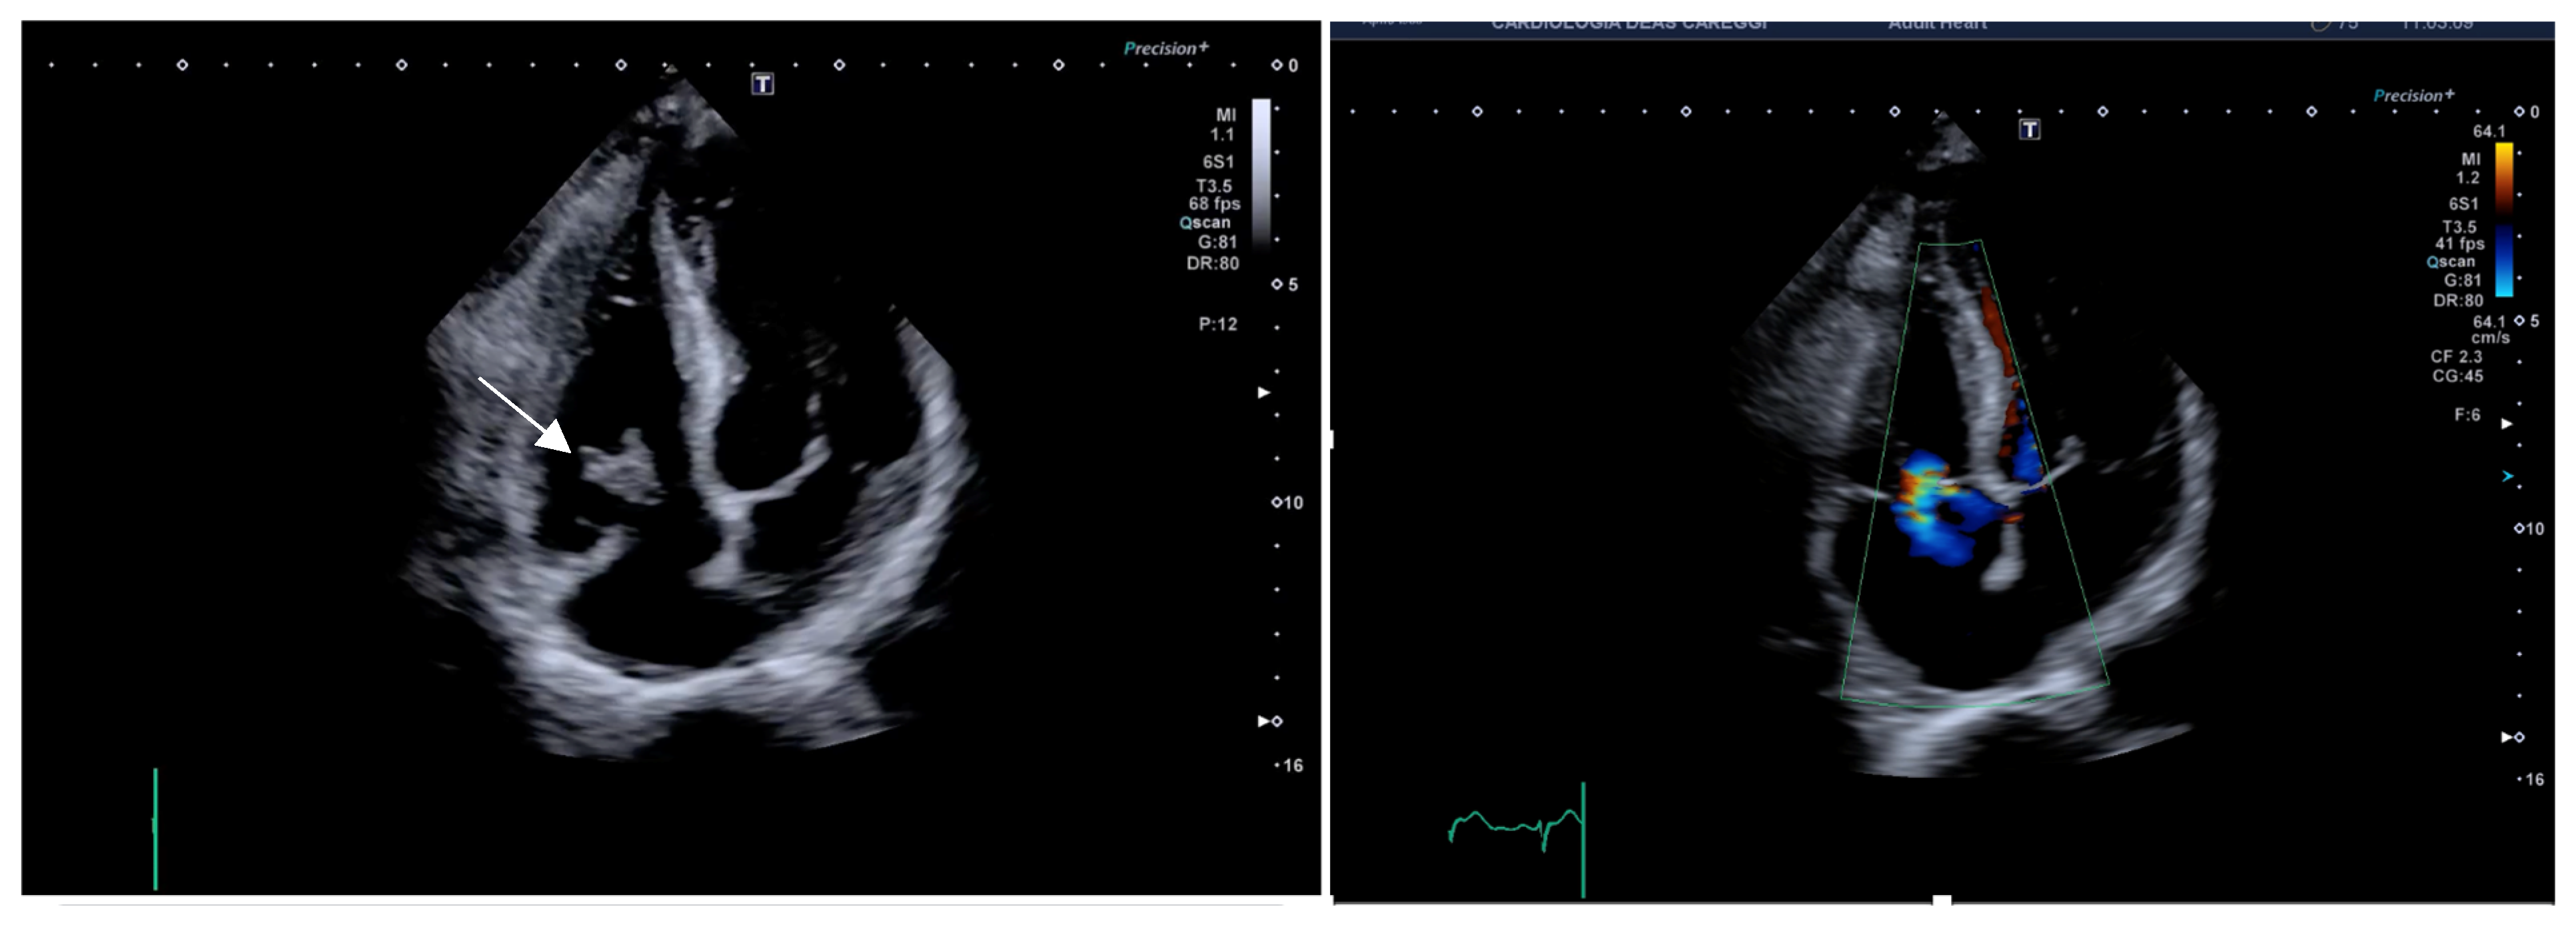

2.1. Case 1

2.2. Case 2

2.3. Case 3